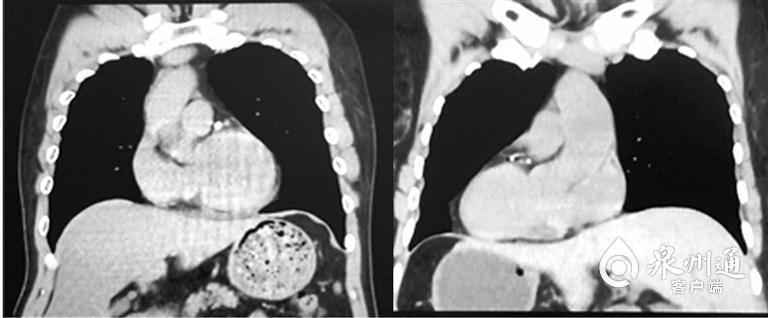

正常人(左)與“鏡面人”CT影像對比

泉州市第一醫(yī)院城東院區(qū)胃腸外科主任陳錦萍說:“正常來說,人的心臟在左側,肝臟在右側。但該患者從腹部到胸部,所有的臟器全部長反了,也就是所謂的‘鏡面人’,即心臟、肝臟、脾臟、膽等器官的位置與正常人相反。在臨床中,這種情況的發(fā)生率僅百萬分之一?!?/span>